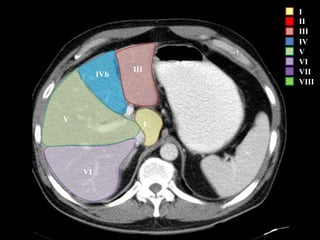

I – Entre cava y porta

II – el más superior de los izquierdos

III – Por debajo del II

IV – por delante de la vesícula

V – por detrás de la vesícula

VI – relación con riñón derecho

VII – el más posterior de los segmentos superiores

VIII – domo hepático

Las claves de la segm. Hepática